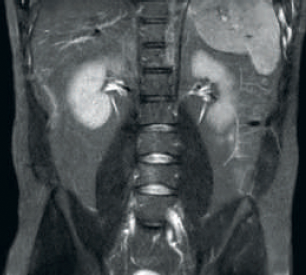

Other RF receive

other receive

Result: Noisy images using identical scan parameters

Result: Improved SNR and image resolution